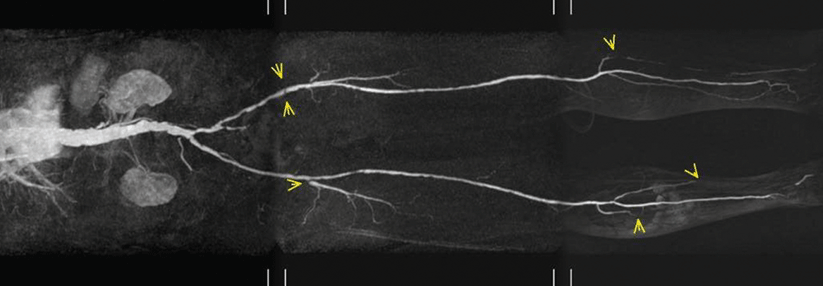

Die Schweizer Pathologen stellten aufgrund dieses Befundes, der Lokalisation und der Anamnese die Diagnose eines „Biker/Radfahrer-Knotens“, auch „akzessorischer dritter Hoden“ genannt. Der medizinische Name lautet perineale noduläre Induration. In der Bildgebung zeigt sich typischerweise eine hypovaskularisierte Läsion, die kein Kontrastmittel aufnimmt.